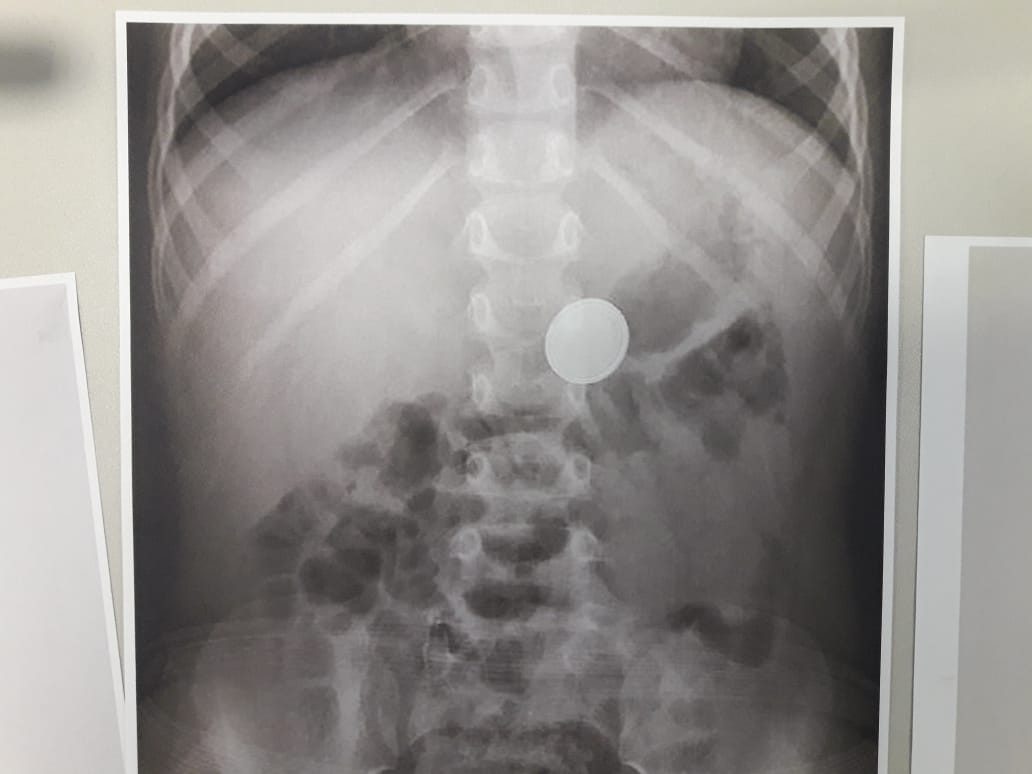

Ребенок проглотил или нет

Ребенок проглотил или нет 103 фотографий